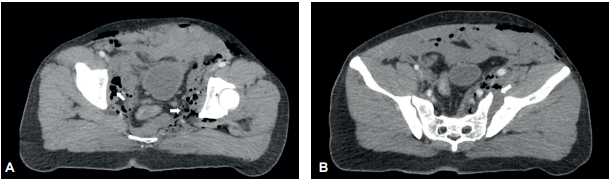

Se inició reanimación con cristaloides, intubación orotraqueal y paso de sonda vesical. Se obtuvieron muestras de laboratorio con hemoglobina de 16 g/dl. Fue llevado a tomografía computarizada de cráneo, tórax y abdomen, documentando gas extraperitoneal, diástasis sacroilíaca izquierda y diástasis severa del pubis (Figura 1).

Figura 1. A: Gas de localización pélvica extraperitoneal por perforación de recto inferior (flechas). B: Diástasis sacroilíaca izquierda (flecha) en paciente a quien también se le documentó diástasis severa del pubis.